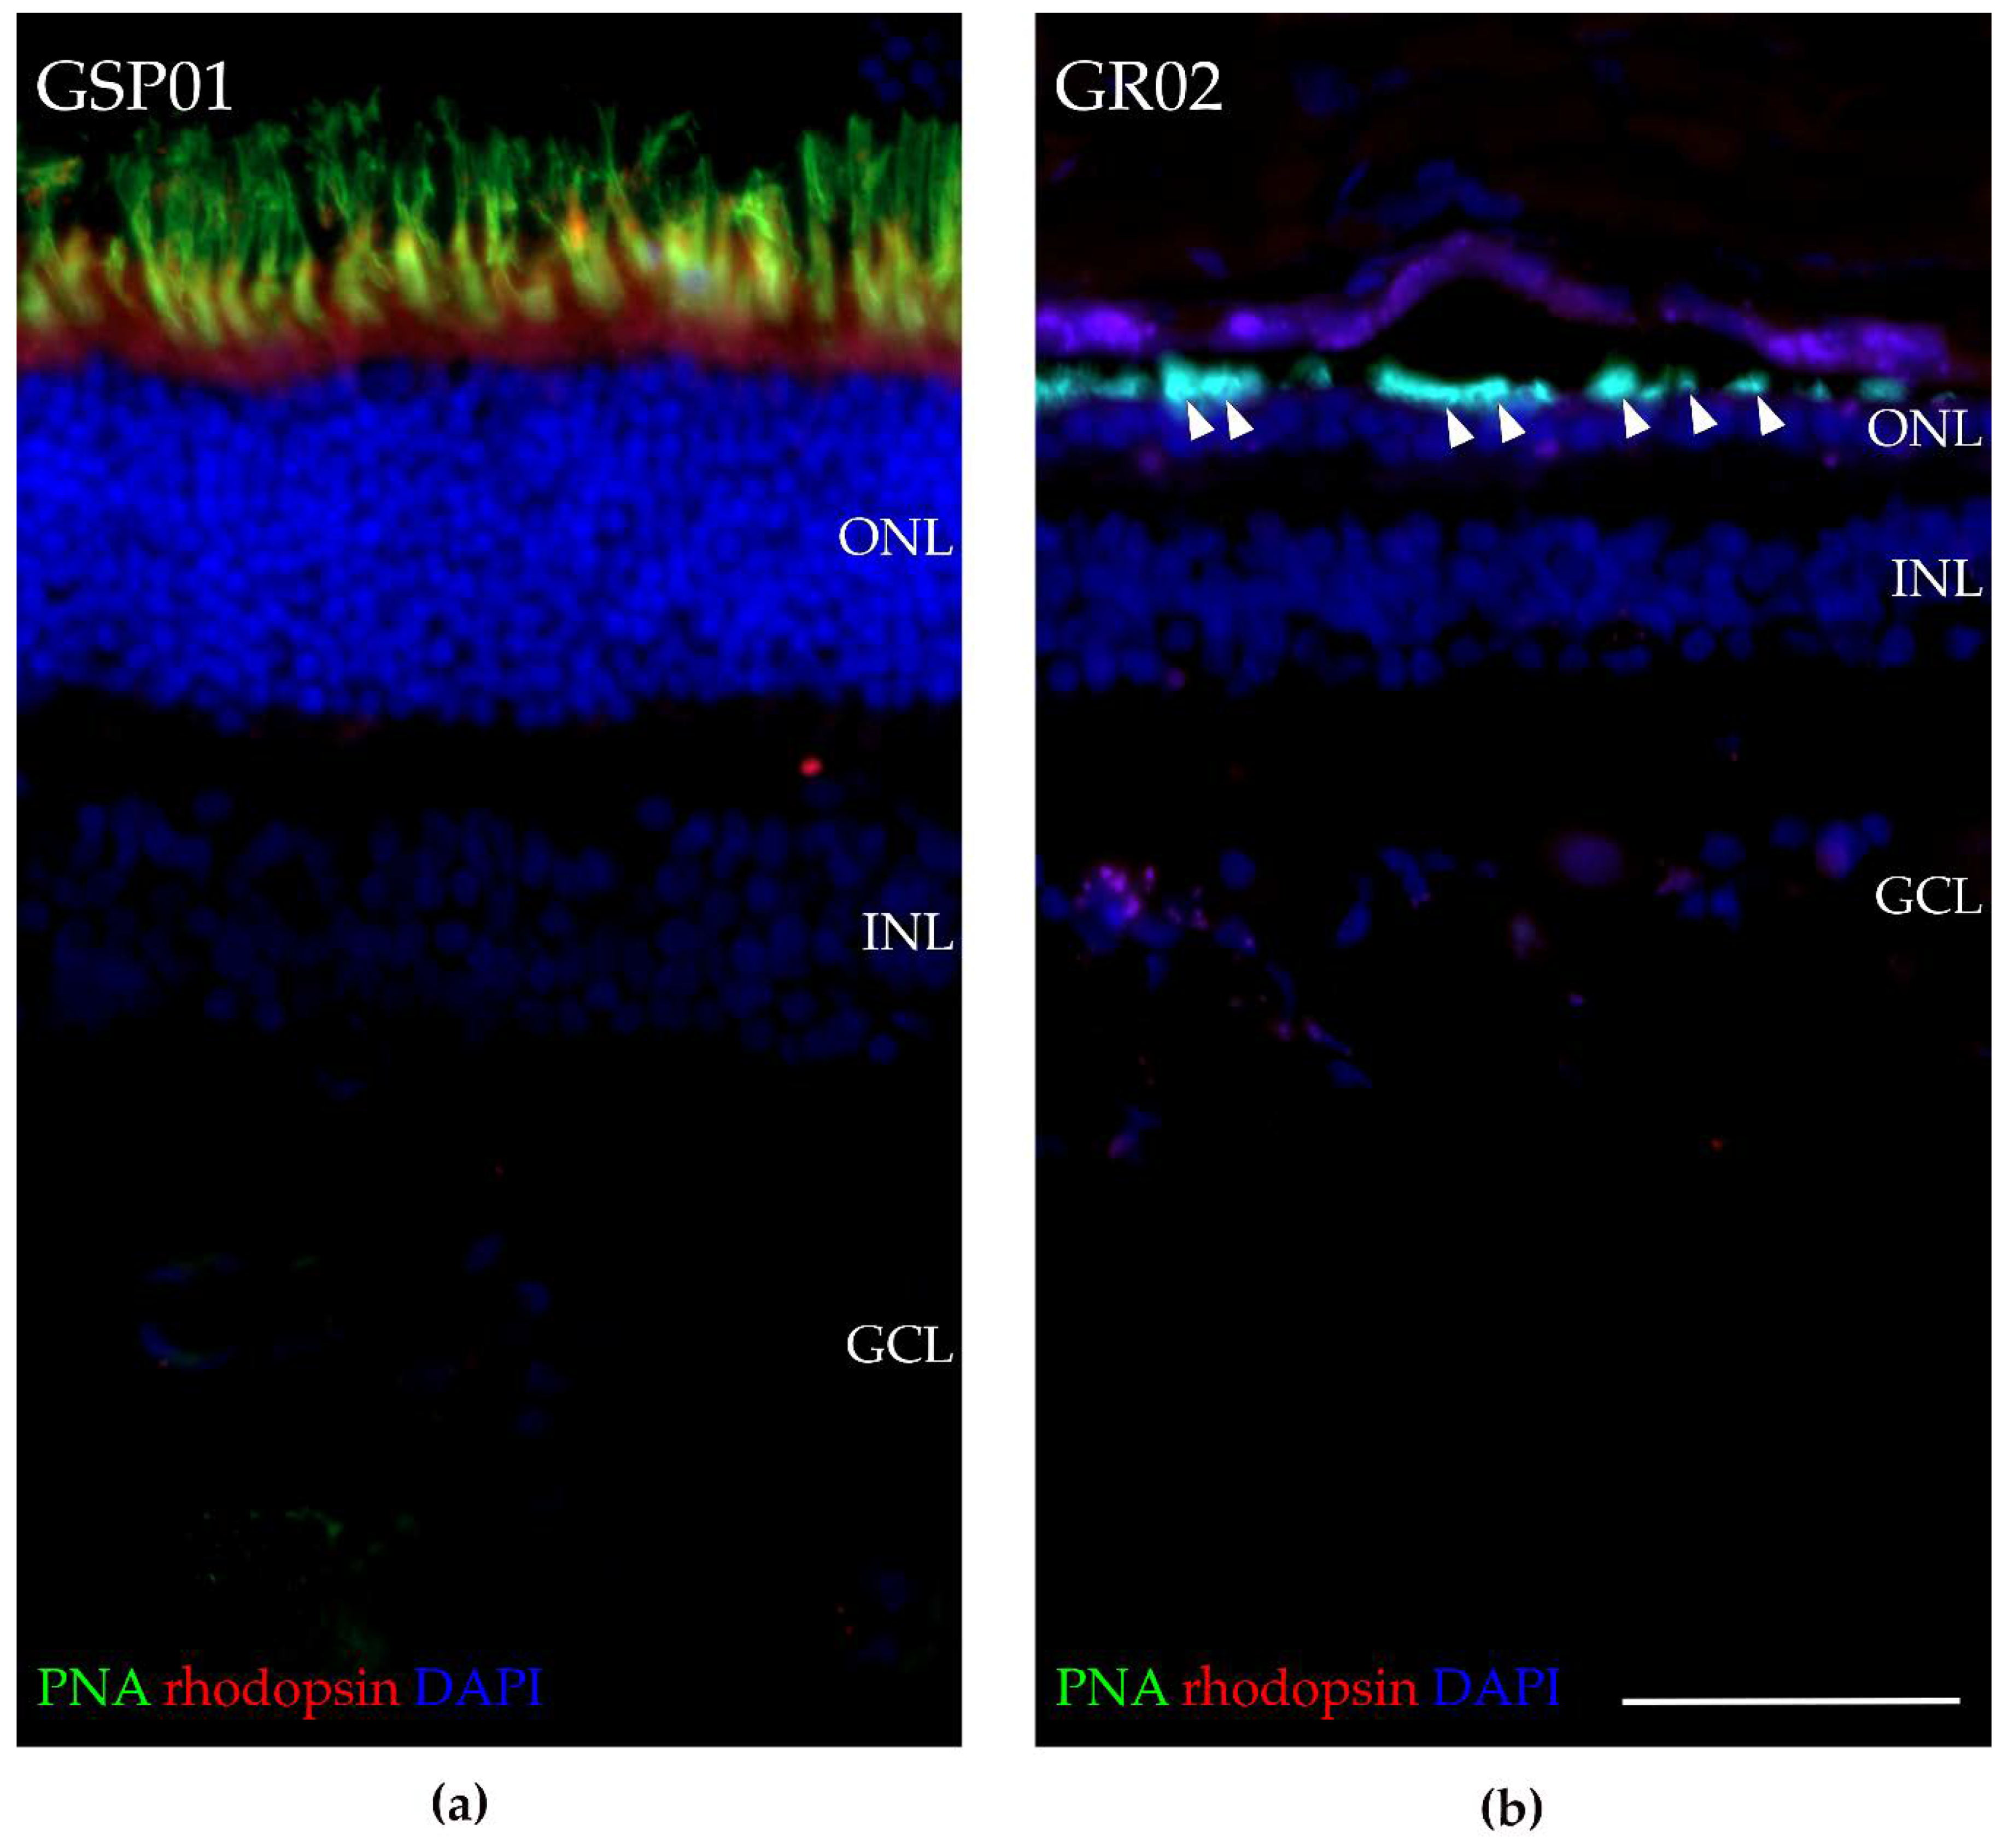

3.8. Fluorescence Histochemical Analysis of the TTC8delA Retina

4. Discussion